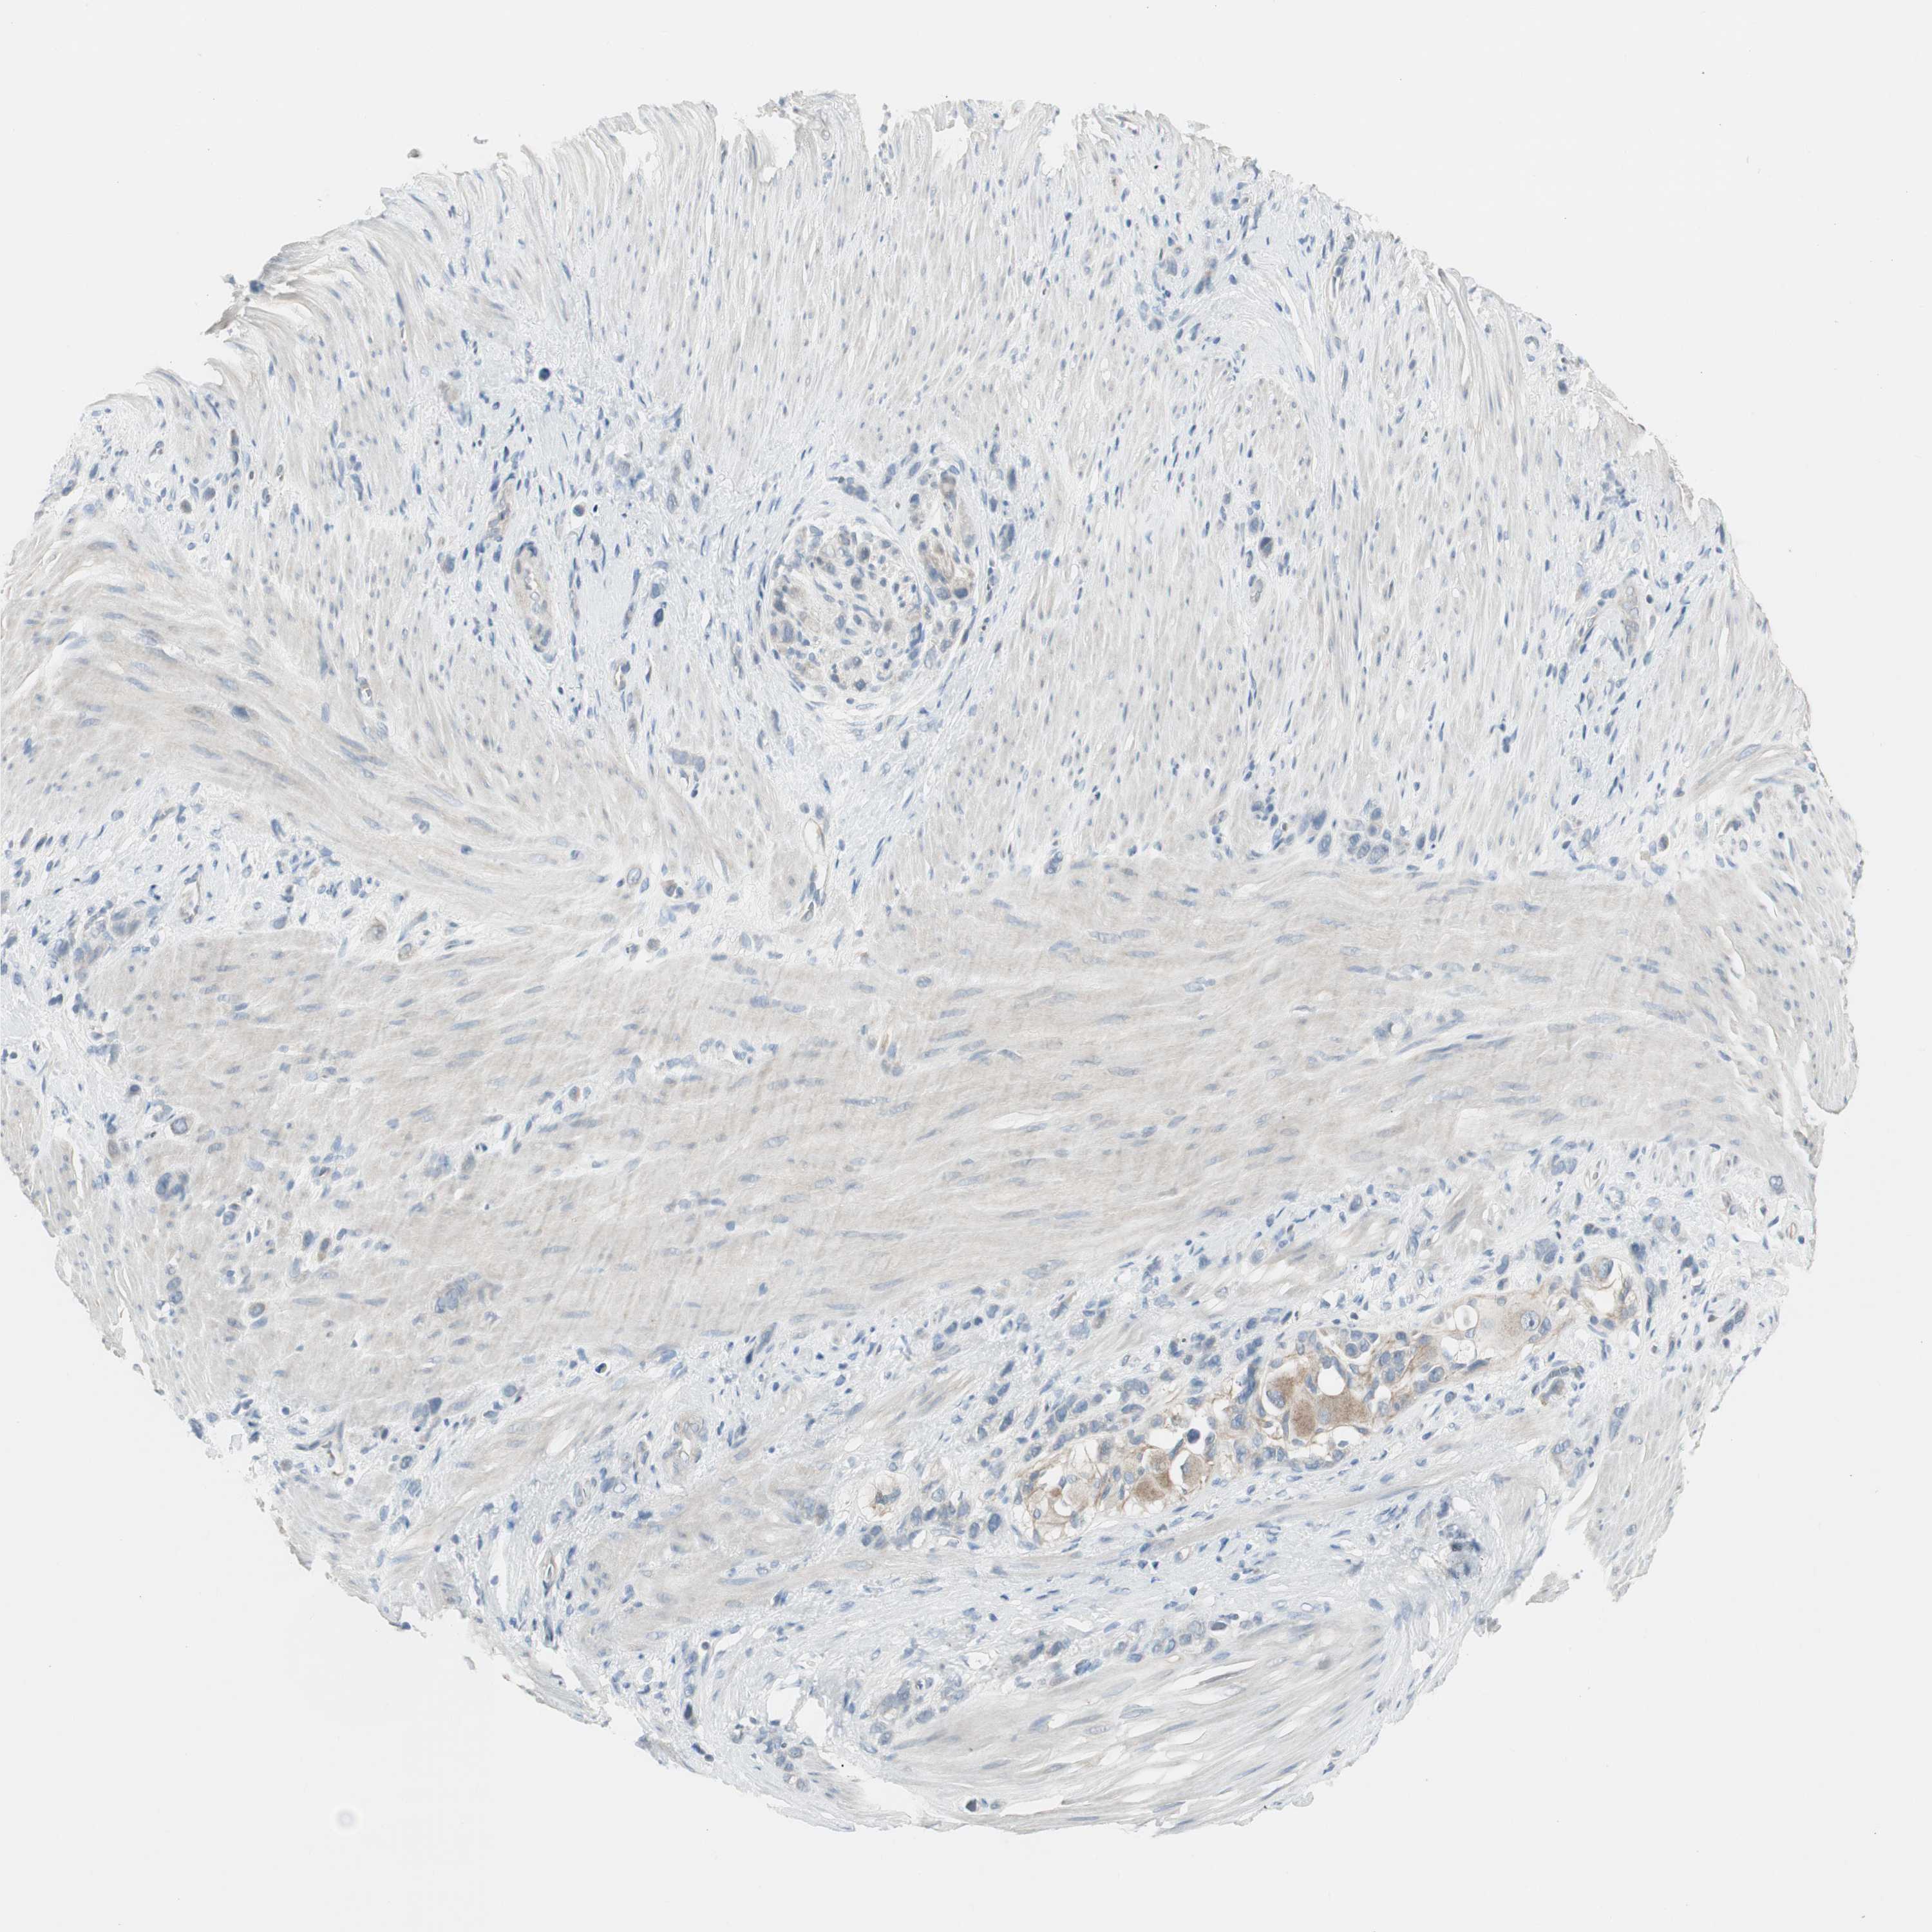

STOMACH CANCER - Protein expressioni

A mouse-over function shows sample information and annotation data. Click on an image to view it in a full screen mode. Samples can be filtered based on level of antibody staining by selecting one or several of the following categories: high, medium, low and not detected. The assay and annotation is described here.

Note that samples used for immunohistochemistry by the Human Protein Atlas do not correspond to samples in the TCGA dataset.

Antibody stainingi

Antibody staining in the annotated cell types in the current human tissue is reported as not detected, low, medium, or high, based on conventional immunohistochemistry profiling in selected tissues. This score is based on the combination of the staining intensity and fraction of stained cells.

Each image is clickable and will lead to virtual microscopy that enables deeper exploration of all samples and also displays staining intensity scores, fraction scores and subcellular localization as well as patient and tissue information for each sample.

Antibody HPA008055

Staining

High

Medium

Low

Not detected

Intensity

Strong

Moderate

Weak

Negative

Quantity

>75%

75%-25%

<25%

None

Location

Nuclear

Cytoplasmic/membranous

Cytoplasmic/membranous,nuclear

Adenocarcinoma, NOS

Adenocarcinoma, High grade